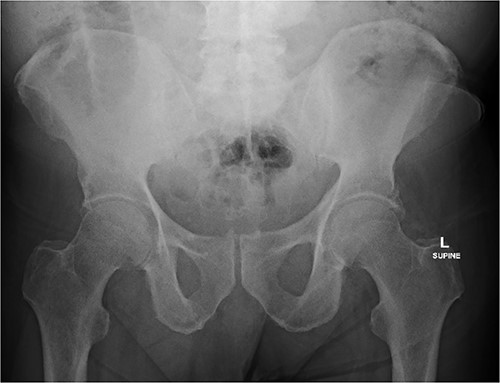

An 80 year old male presented to the emergency department after accidentally swallowing his hearing aids. On presentation he was pain free, hemodynamically stable, and had a soft abdomen. He had a background of type-2 diabetes, rheumatoid arthritis and diverticulitis. The hearing aids were powered by lithium battery. X-ray found two foreign bodies in the left upper abdomen (Fig. 1). After assessment in the emergency department, he returned home to await their natural passage. One hearing aid was found in his stools the following day, but he represented three weeks later as the second hearing aid remained unaccounted for. He underwent repeat abdominal x-ray and CT, which found the hearing aid retained within a presumed distal duodenal diverticulum (Figs 2 and 3). He was booked a push enteroscopy the following day.

Abdominal CT identifying one hearing aid in a jejunal diverticulum 3 weeks after initial presentation – coronal view.